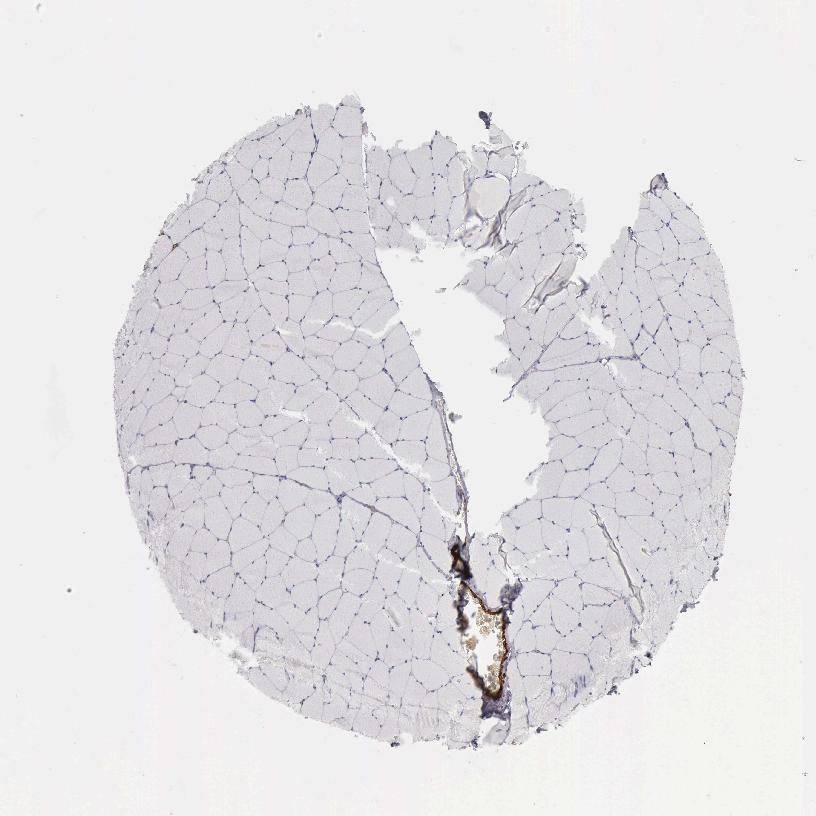

SKELETAL MUSCLE - Antibody stainingi

Antibody staining in the annotated cell types in the current human tissue is reported as not detected, low, medium, or high, based on conventional immunohistochemistry profiling in selected tissues. This score is based on the combination of the staining intensity and fraction of stained cells.

Each image is clickable and will lead to virtual microscopy that enables deeper exploration of all samples and also displays staining intensity scores, fraction scores and subcellular localization as well as patient and tissue information for each sample.

Antibody HPA008066Antibody HPA017330Antibody CAB000006

Myocytes Not detectedNot detectedNot detected